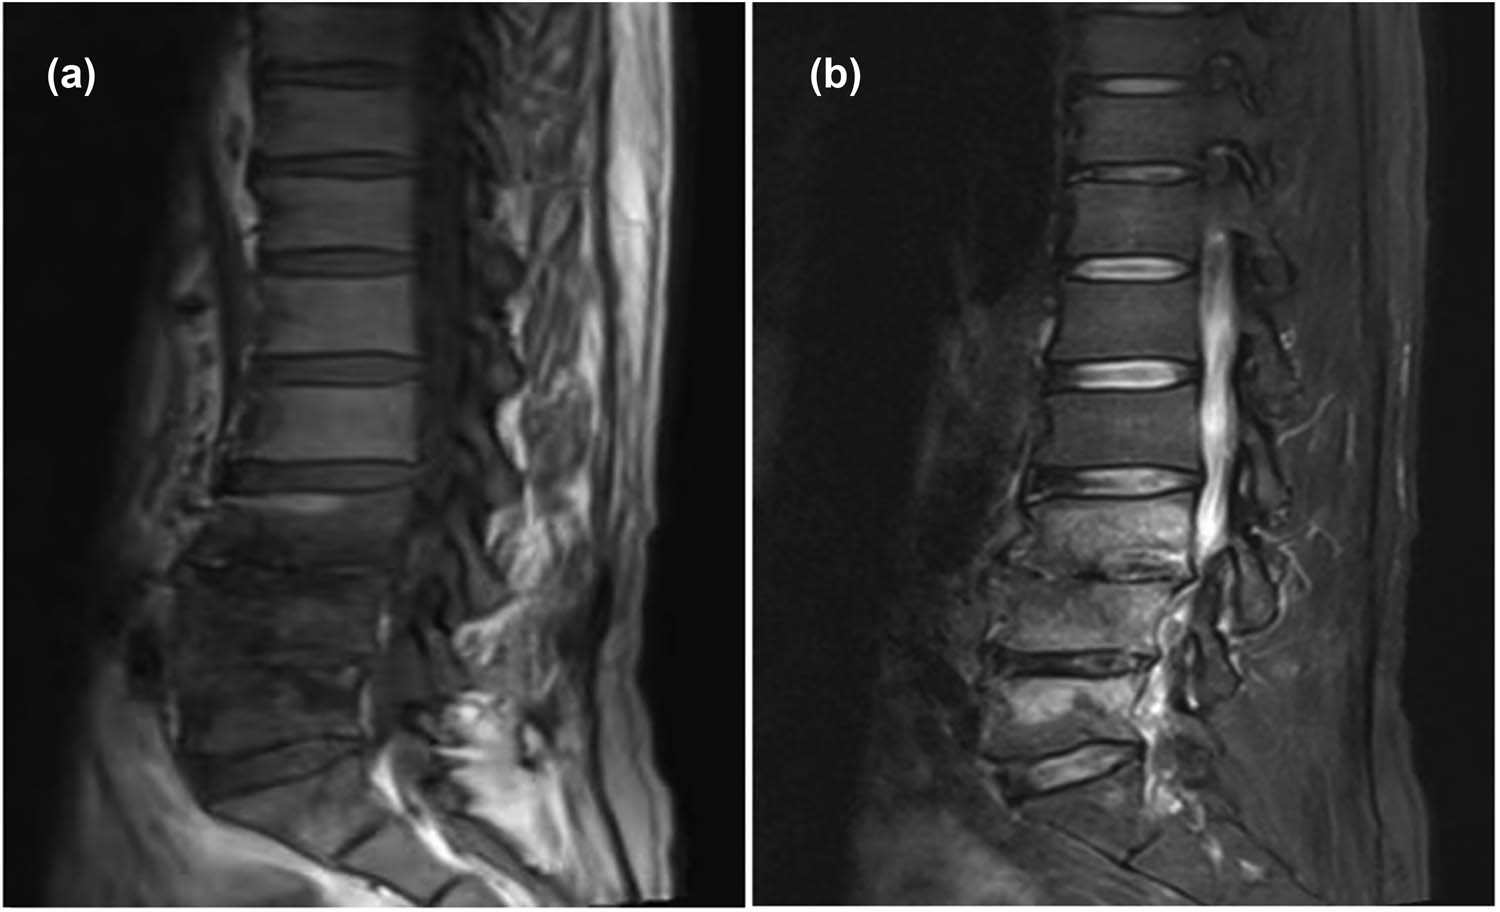

Initial high-resolution computed tomography (CT) scan of the chest at admission revealed right hilar occupation, extensive mediastinal lymphadenopathy, minimal bilateral pleural effusions, coronary artery calcification, and slight pericardial effusion, along with a high-density shadow localized to approximately the T7 vertebra (Figure 1a). Pre-discharge CT re-evaluation demonstrated marked improvement relative to prior findings (Figure 1b). During the initial bronchoscopy, examination of the lower tracheal segment revealed notable findings including fish-scale-like alterations on the mucosa, a blunted carina, and infiltrative changes, suggesting extensive mucosal involvement. An abnormal growth completely obstructed the lumen at the opening of the right main bronchus, while another lesion was identified on the wall of the left main bronchus, with its distal end remaining patent. Electric loop excision was performed on the right main bronchus to remove the obstructing lesion. This procedure revealed extensive abnormal extension to the distal end of the bronchus, obscuring the openings of the upper and lower lobes. Subsequent irrigation of the bronchus was performed to ensure cleanliness and assess clearance (Figure 2a). A follow-up bronchoscopy conducted a week later revealed polypoid hyperplasia on the inner wall of the left main bronchus and a spherical lesion at the opening of the right main bronchus. Following snare excision of the right bronchial lesion, further examination observed that the growth extended to the terminal end of the bronchus (Figure 2b). Lumbar spine MRI findings: Abnormal signal in L3–L5 vertebrae, suggesting infectious lesions, with posterior spondylolisthesis of L3 and L4 vertebrae (Grade I) and degenerative changes in the lumbar spine (Figure 3).

Lumbar spine MRI indicates abnormal signal intensity in the L3–L5 vertebral bodies with low signal on T1-weighted images (a) and high signal on T2-weighted images (b), suggestive of an infectious lesion.

Brucellosis, attributable to the Gram-negative Brucella bacterium, exhibits widespread prevalence across diverse regions including the Middle East, the Mediterranean, Central Asia, and Latin America. Transmission of the disease to humans occurs primarily through direct contact with infected animals or via consumption of contaminated animal products, particularly unpasteurized milk and cheeses [22]. As the disease progresses, clinical manifestations of brucellosis vary, initially presenting with symptoms such as fever, muscular pain, arthralgia, and fatigue. In more severe cases, the infection may affect visceral organs such as the liver, spleen, and CNS, with the spine predominantly involved, leading to brucellar spondylitis [23]. This condition is characterized by typical clinical presentations, including persistent, intense lower back pain, fever accompanied by profuse sweating, and evident signs of infection in the spinal intervertebral discs and vertebral bodies [24]. Regarding treatment, it generally entails a prolonged regimen of combined antibiotics to prevent relapse [25]. From a diagnostic perspective, radiologically, it is crucial to differentiate vertebral lesions caused by brucellosis from those due to spinal tuberculosis and pyogenic spondylitis. Patients diagnosed with brucellar spondylitis typically exhibit low signal intensity on T1-weighted imaging and high signal intensity on T2-weighted imaging [26], aligning with the MRI findings observed in this case. According to the World Health Organization, a regimen of doxycycline with rifampin or doxycycline with streptomycin is recommended for treating Brucella, supplemented by ceftriaxone or levofloxacin in refractory or severe cases, alongside hepatoprotective and supportive therapies. In instances where conservative treatments fail, surgical intervention may be warranted for cases exhibiting spinal cord or nerve root compression, vertebral instability, or a risk of paralysis.